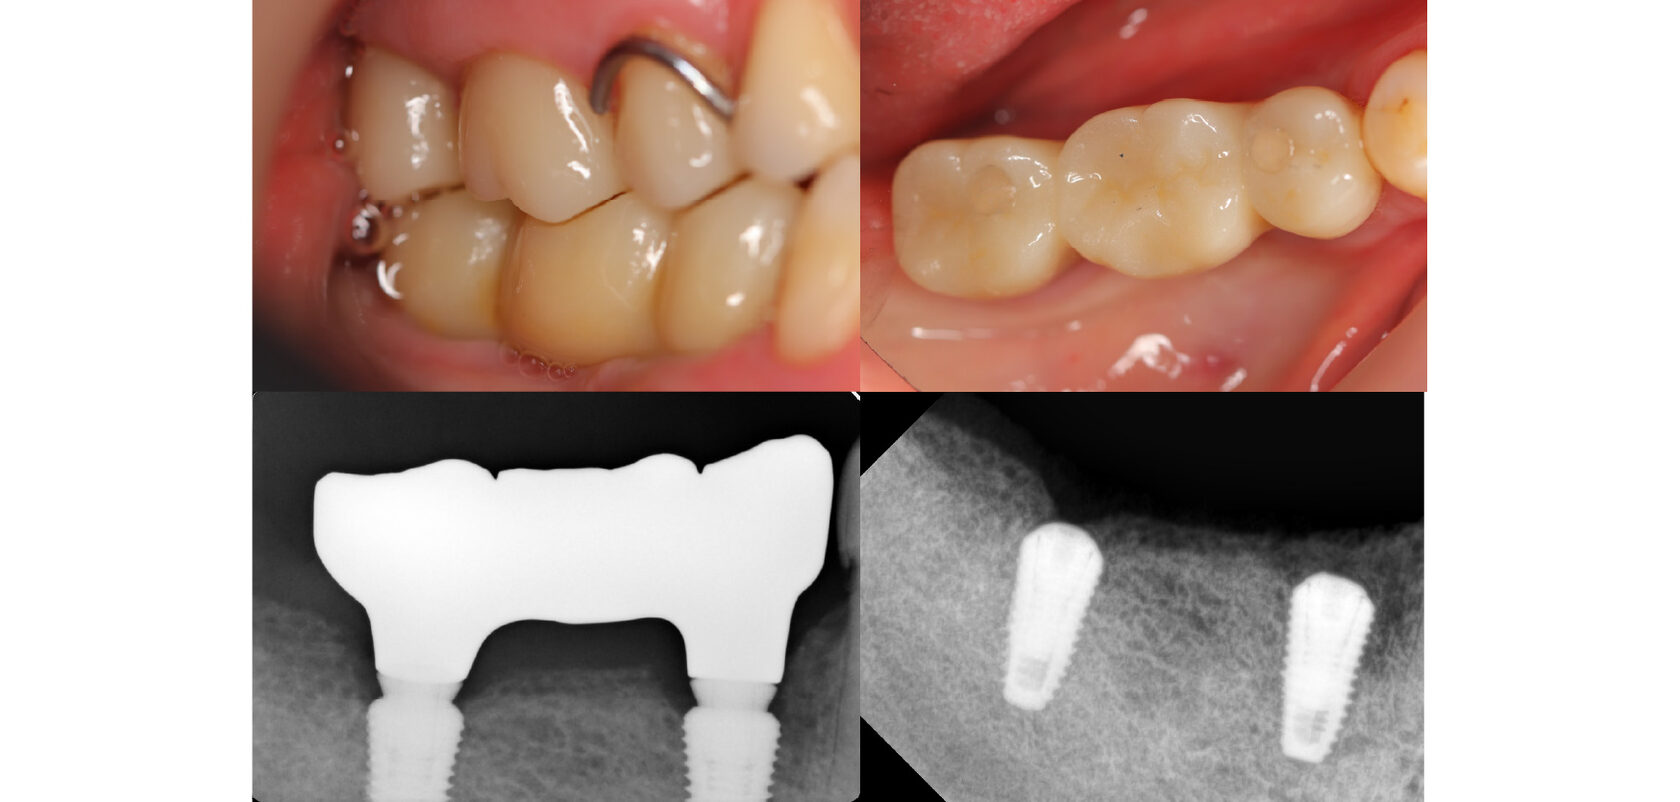

Далее пациент был направлен хирургу имплантологу, для установки двух имплантатов справа.

Слева зубной ряд закончился на седьмом зубе.

В итоге: полная реабилитация: удаление разрушенных зубов, лечение кариозных, укрепление коронками и протезирование обеих челюстей! Жевание, удобство, улыбка, всё есть!